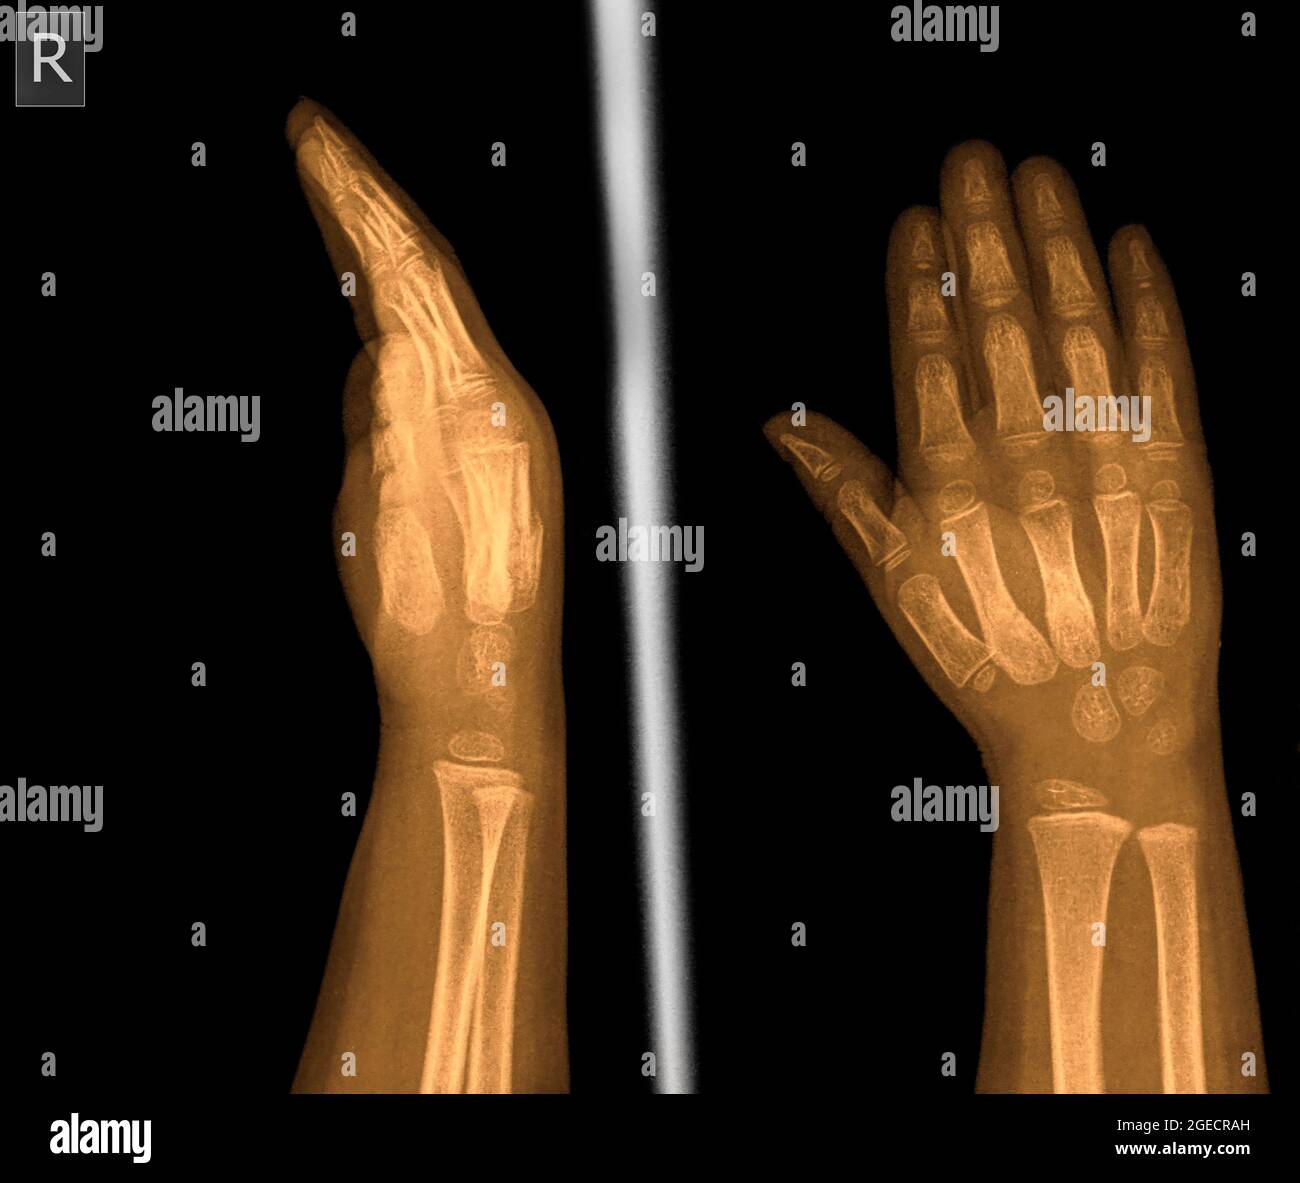

Prepare to be captivated by Top, a showcase of x ray of right hand and wrist imagery powered by wonderkidsmontessori.edu.vn. More related visuals are below.

x ray of right hand and wrist

Posts: x ray of right hand and wrist